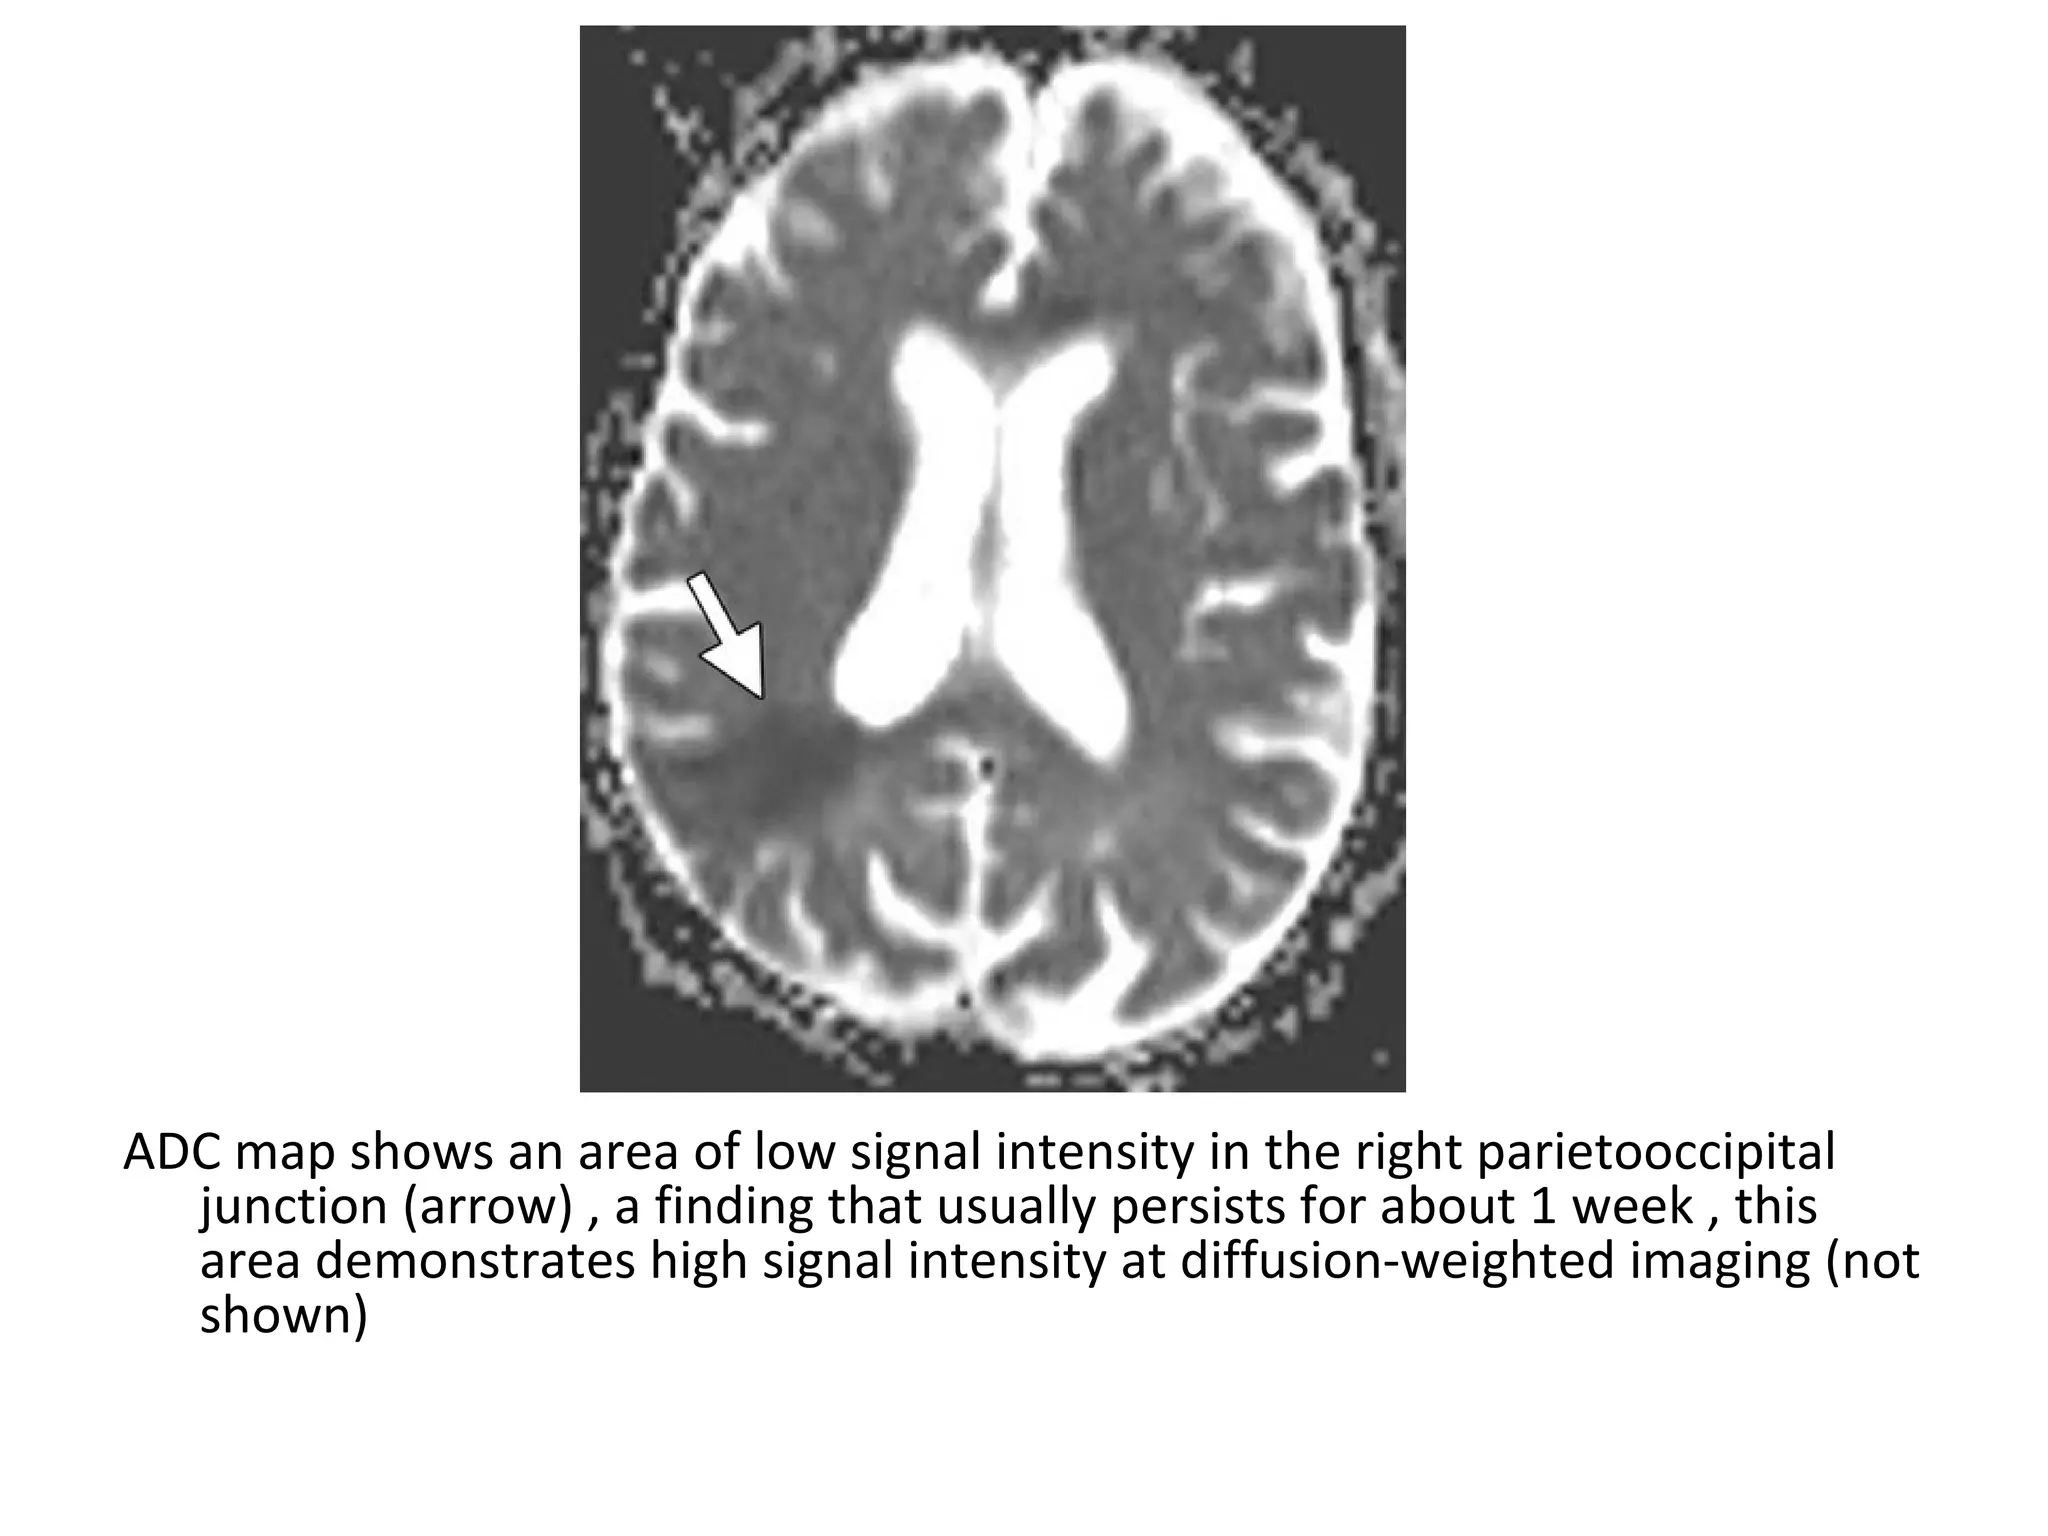

ADC map shows an area of low signal intensity in the right parietooccipital

junction (arrow) , a finding that usually persists for about 1 week , this

area demonstrates high signal intensity at diffusion-weighted imaging (not

shown)